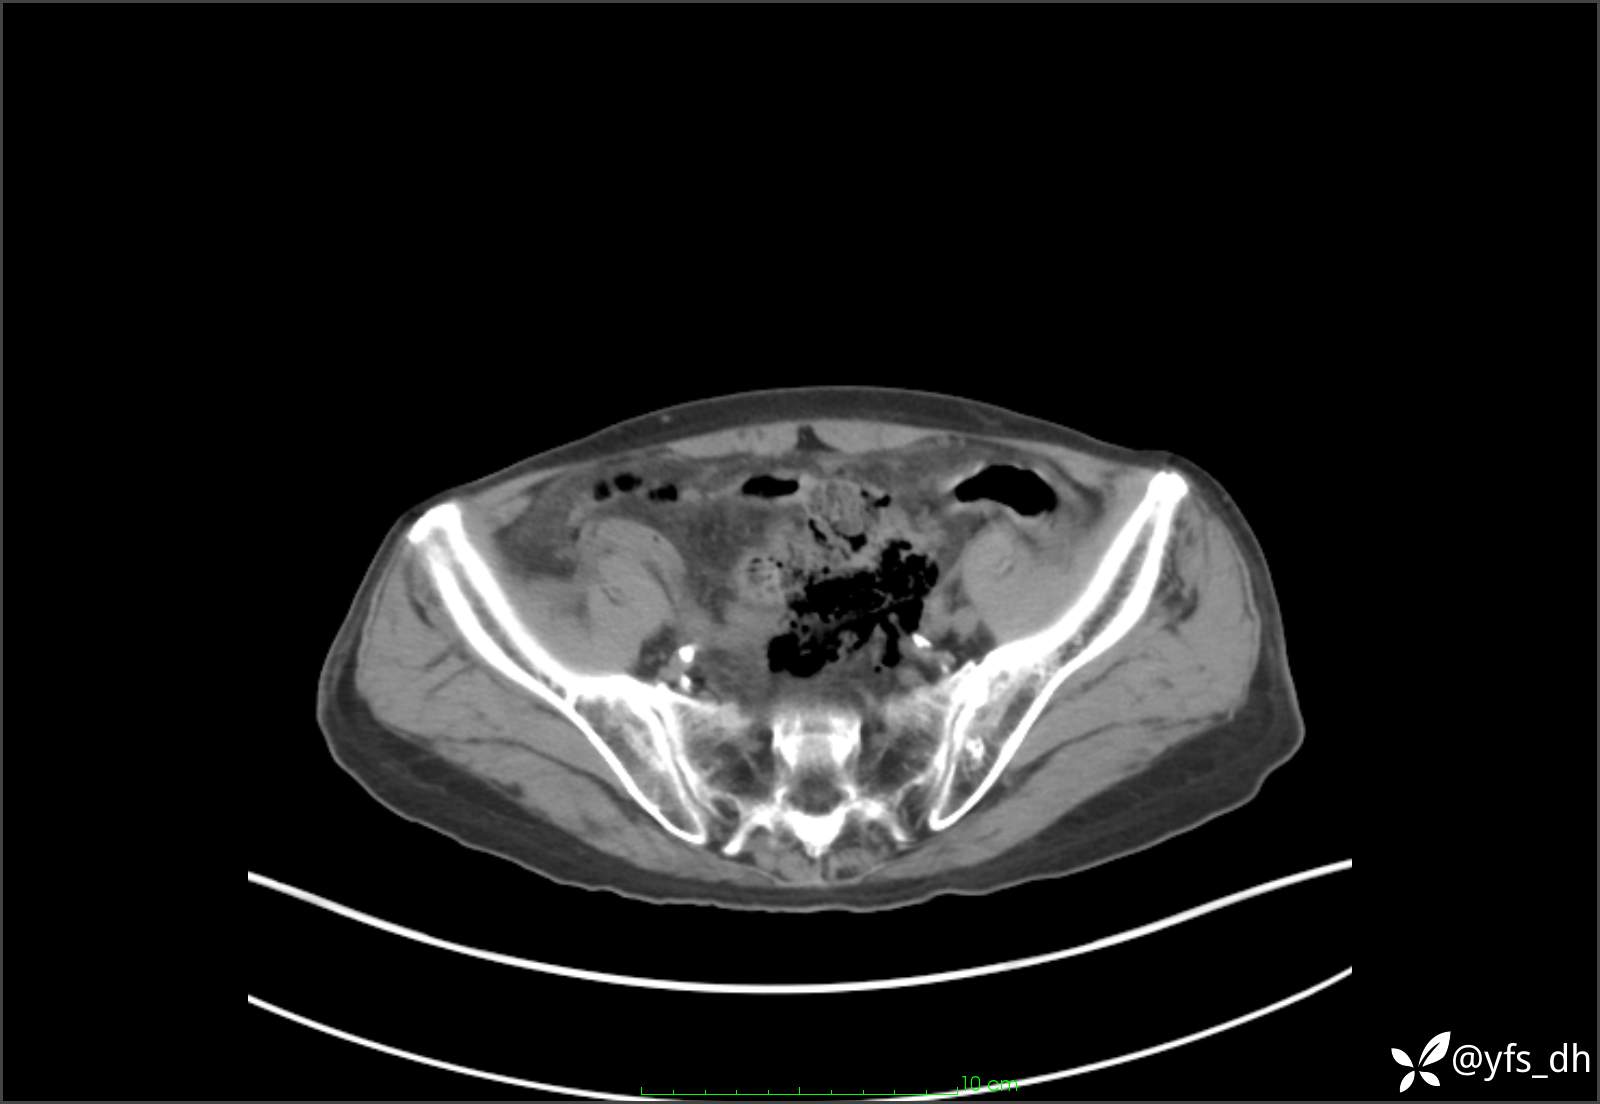

1.简要病史:患者4天前突发上腹部疼痛不适,但可以忍受。3小时前饭后突然加重,不能忍受后就诊。

2.简要手术记录:术中见腹盆腔大量肠液及粪便,乙状结肠中下段见一约3cm的破口。